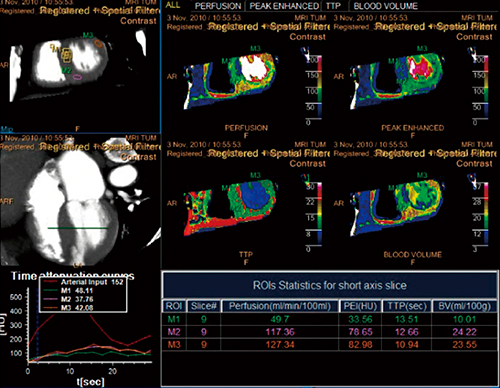

■Dynamic Myocardial Perfusion

心筋の機能を評価する方法として心筋CT Perfusionがあり,フィリップスでは独自に“Dynamic Myocardial Perfusion”(以下,DMP)を開発した。フィリップス社製CT「Brilliance iCT Elite」は,256スライスのデータ収集を可能としたCTである。検出器幅は80mmに広がり,心筋全体を1回転でデータ収集することが可能である。ガントリ回転速度は0.27秒/回転であり,モーションアーチファクトの少ない画像を寝台移動させることなく得ることが可能となっている。DMPで得られたデータはボリュームデータであるため,撮影後,任意の断面やスライス厚に再構成し評価を行うことが可能である。加えて,心尖部から心基部までの範囲のデータを一度のスキャンで収集しているため,各時相の血流情報をボリュームで得ることができる(図1)。そのため,正確な評価を行うことも可能である。DMPの解析は,フィリップスのマルチモダリティ解析ワークステーションである「IntelliSpace Portal」(以下,ISP)に搭載されている。

図1 Dynamic Myocardial Perfusion